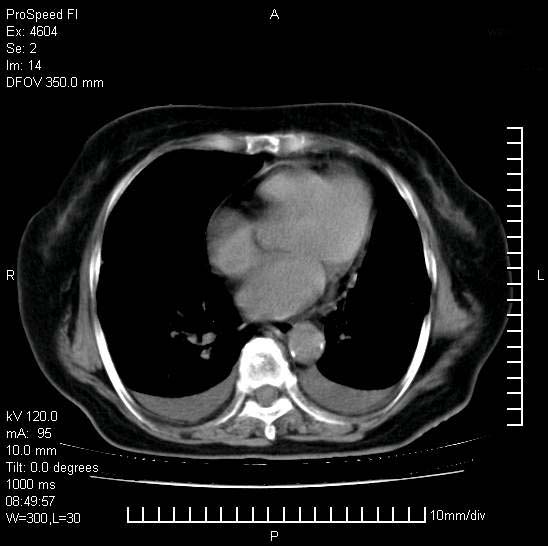

十几年前曾患肺结核,一周前突咳血约100ml,中性粒细胞稍高,诊断两上肺陈旧结核,下肺炎症,给予抗炎治疗,近几日晚上高热,39度,仍咳少量血,4天前ct及今天ct上传。

[face=黑体]8月30日[/face]

今天ct

支持陈旧性肺结核并两下肺感染,两侧胸腔积液。

短短几天内,病变范围明显增多扩大,以左侧明显,而且双侧出现胸水,还是考虑感染.

短短几天内,病变范围明显增多扩大,以左侧明显,而且双侧出现胸水,我更多考虑左侧中心性肺癌并并阻塞性不张及肺炎,炎症变化也太快了!

1)两肺结核并感染。2)不排除左肺上叶中央型肺癌并阻塞性肺炎、肺不张可能;建议行纤支镜检查。3)右肺门及纵隔淋巴结肿大。4)双侧胸腔积液。